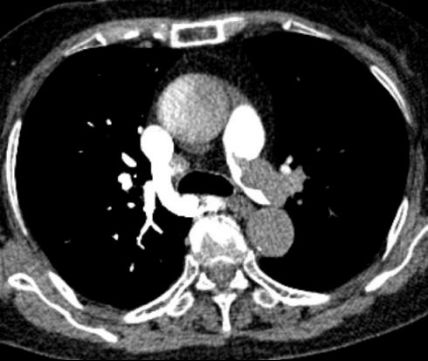

急診醫(yī)生快速研判,高度懷疑為急性肺栓塞。肺動(dòng)脈CTA檢查結(jié)果證實(shí)了判斷:雙側(cè)肺動(dòng)脈主干及分支存在多處血栓栓塞,右心室明顯擴(kuò)大——這是急性肺栓塞的典型征象,說明肺動(dòng)脈堵塞已導(dǎo)致右心室負(fù)荷急劇增加,心臟功能受損。

圖:胸部增強(qiáng)CT(CTPA)示右肺動(dòng)脈主干及分支內(nèi)可見多發(fā)充盈缺損提示肺動(dòng)脈栓塞